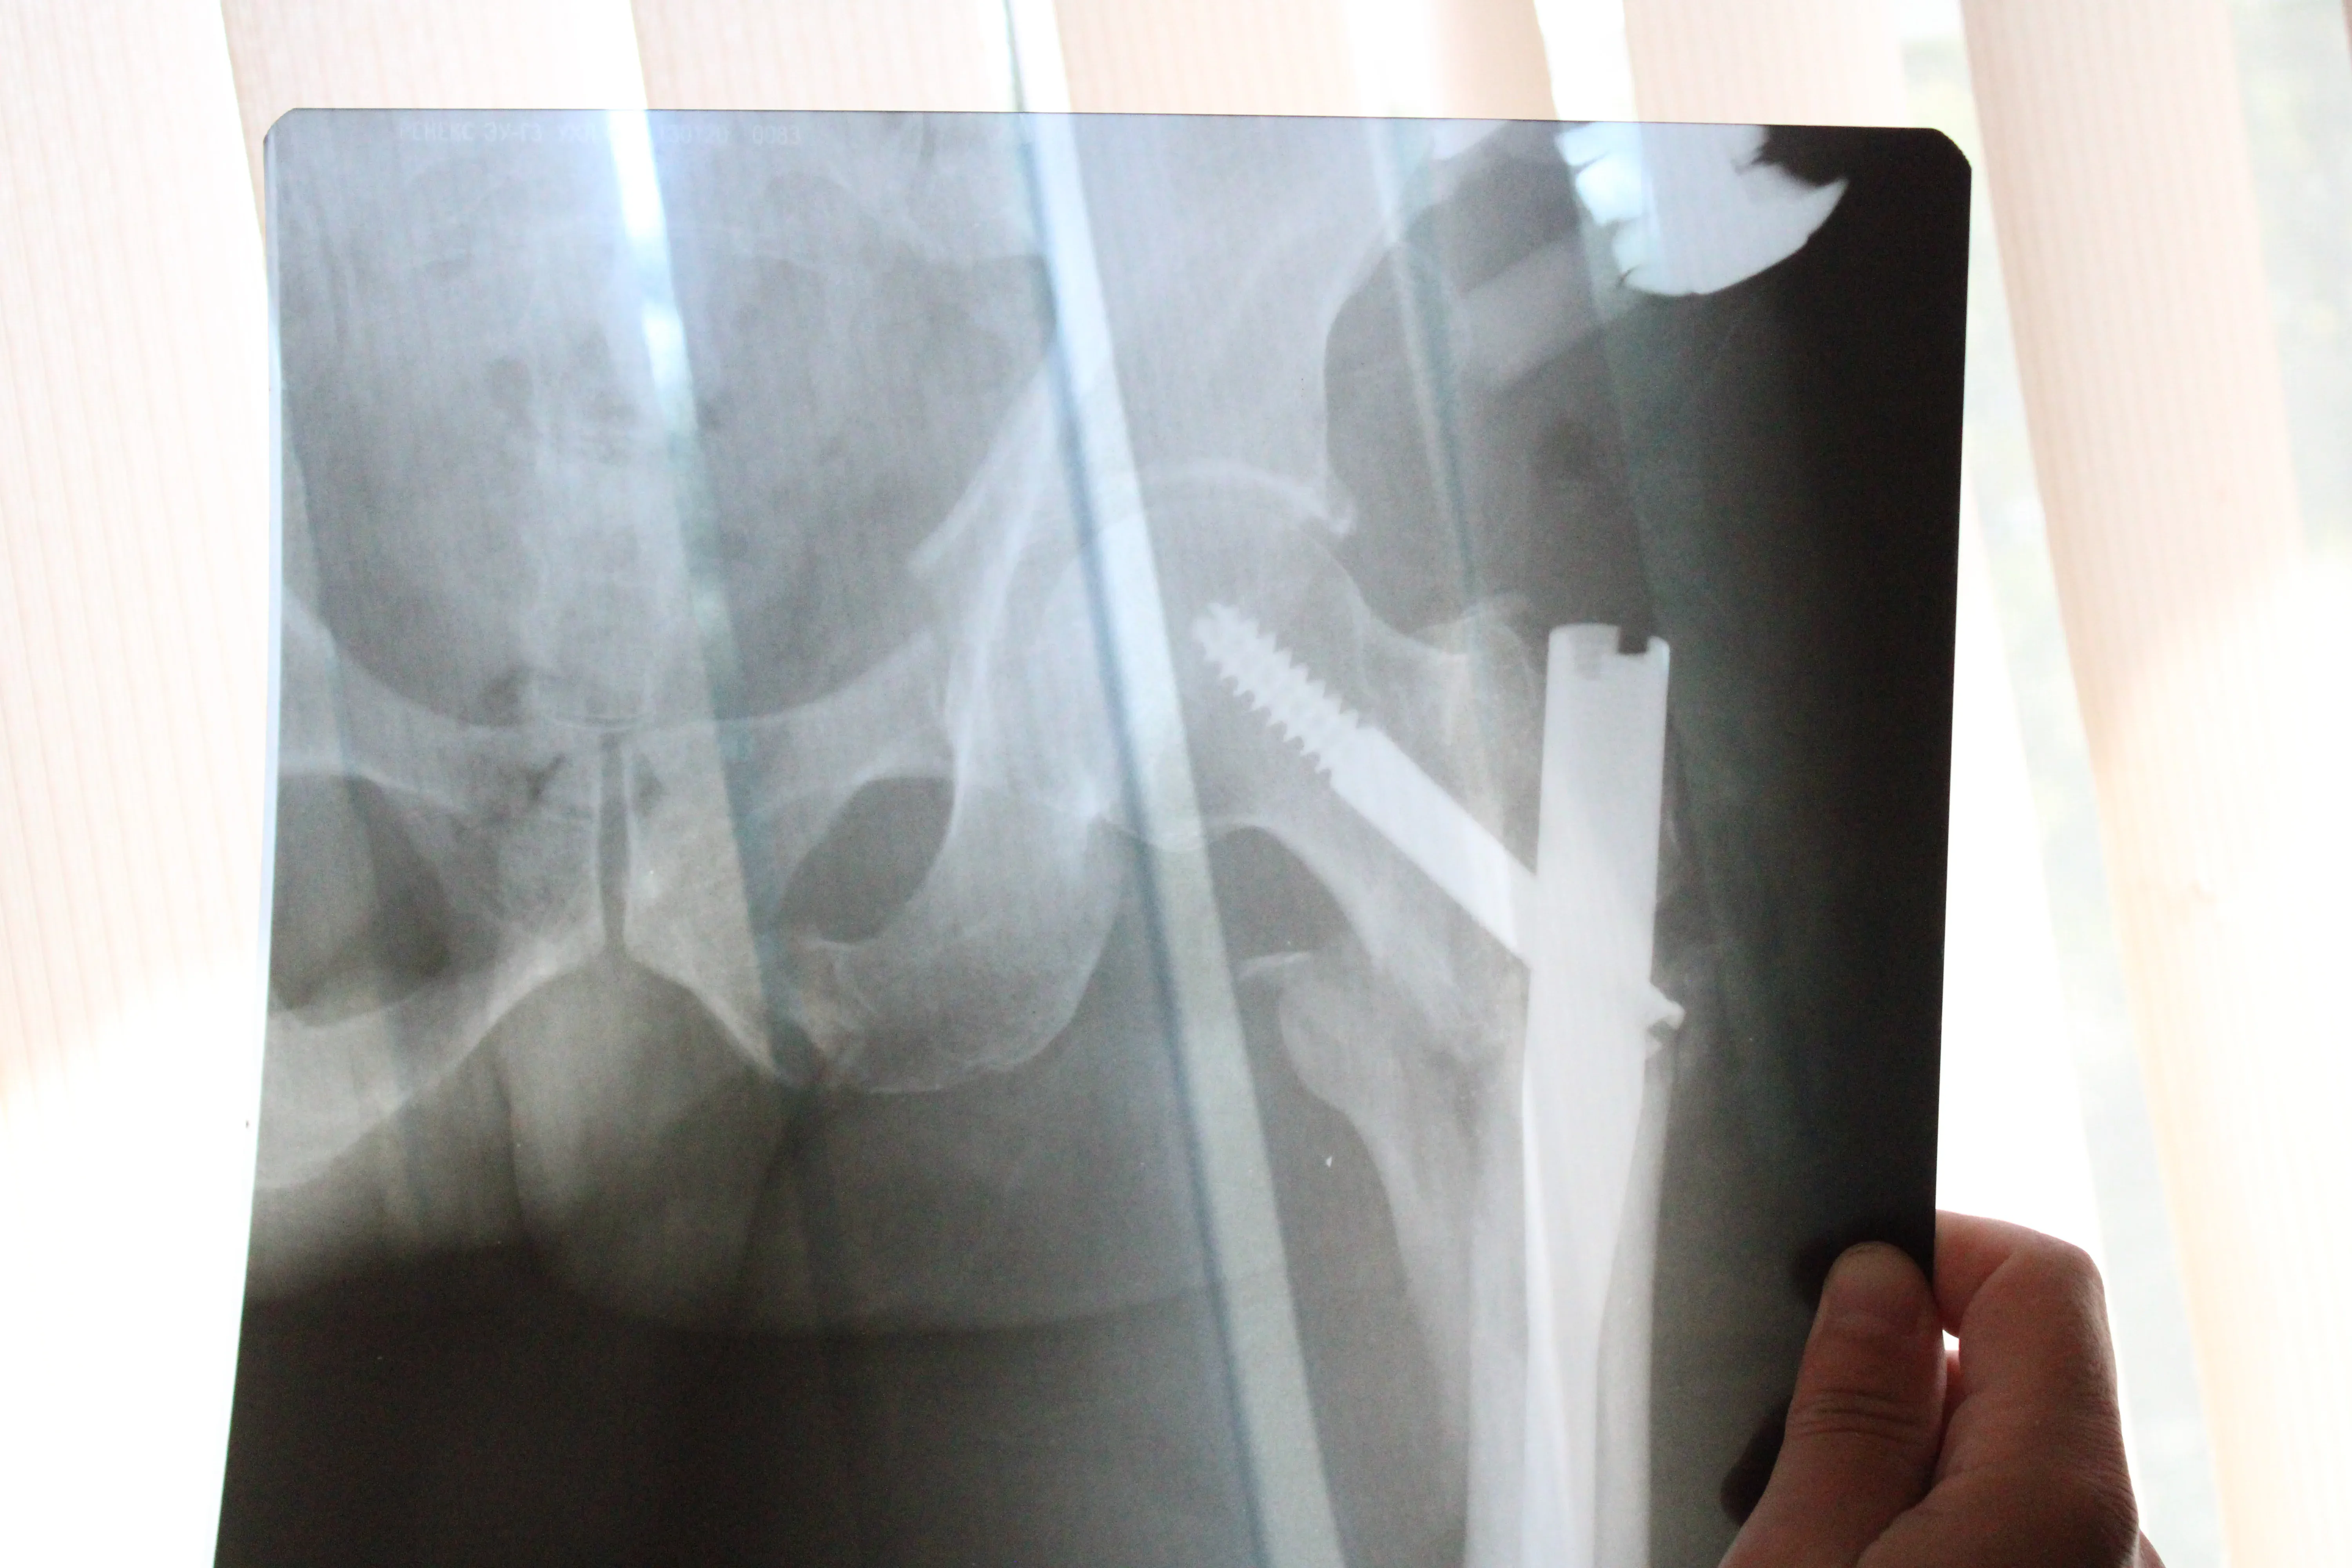

"Состояние пациента при поступлении было тяжелым: перелом левого бедра, перелом костей таза и правой пяточной кости. У него был травматический шок 3-й степени, давление 70 на 40", – сообщил травматолог-ортопед нейрохирургического отделения БСМП Сергей Казенов.

Три дня Павел провел в реанимации, где его состояние было стабилизировано. 11 июля ему провели операцию. Бригада медиков под руководством заведующего нейрохирургическим отделением Леонида Овечкина несколько часов восстанавливала многочисленные костные отломки.

Врачи сумели сохранить анатомическую структуру костей, их длину и ротацию. Прогнозы – благоприятные.